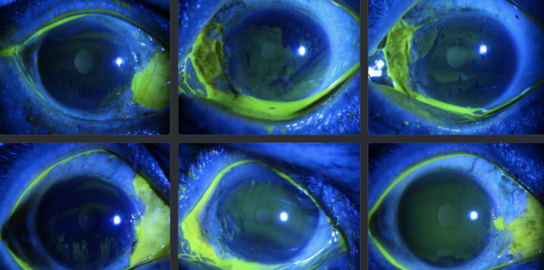

眼病深度学习数据集

数据集下载地址:http://m6z.cn/5yth3m

712张片状角膜溃疡的眼部染色图像